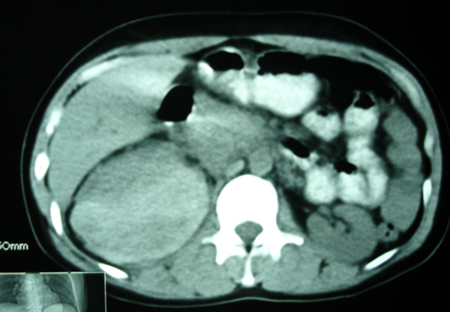

以下是引用bmw011在2009-4-23 13:28:00的发言:[br]考虑右肾包膜下血肿。

以下是引用卜一在2009-4-23 15:43:00的发言:[br]考虑右肾包膜下血肿,不排除占位病变伴出血可能,建议进一步检查。